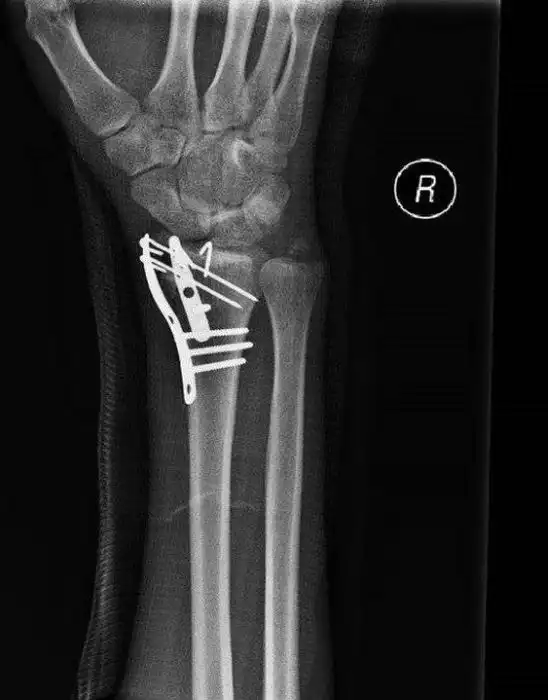

После просмотра этих фотографий вам будет трудно поверить в то, что мотоциклист выжил, всего лишь сломав руку в нескольких местах.